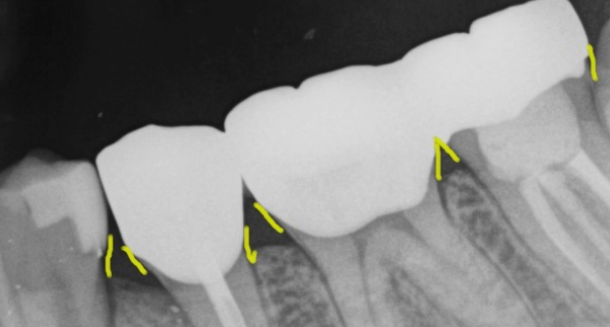

2) 뿌리 끝 염증으로 나타나는 통증

치아 신경치료 후 뿌리 끝에 염증이 생기며 통증이 나타나는 경우도 있어요. 신경치료가 잘 되었음에도 뿌리끝에 염증이 생기는 경우가 있는데요, 이는 복잡한 구조로 제거할 수 없는 근관속 염증이 뿌리끝에 모이게 되면서 잇몸이 부었다 가라앉았다를 반복하는 경우, 통증이 생기는 경우 등의 증상이 생기게 되며 치료방법으로는 치아 재식술 or 임플란트를 통해 치아의 기능을 회복하기도 해요.